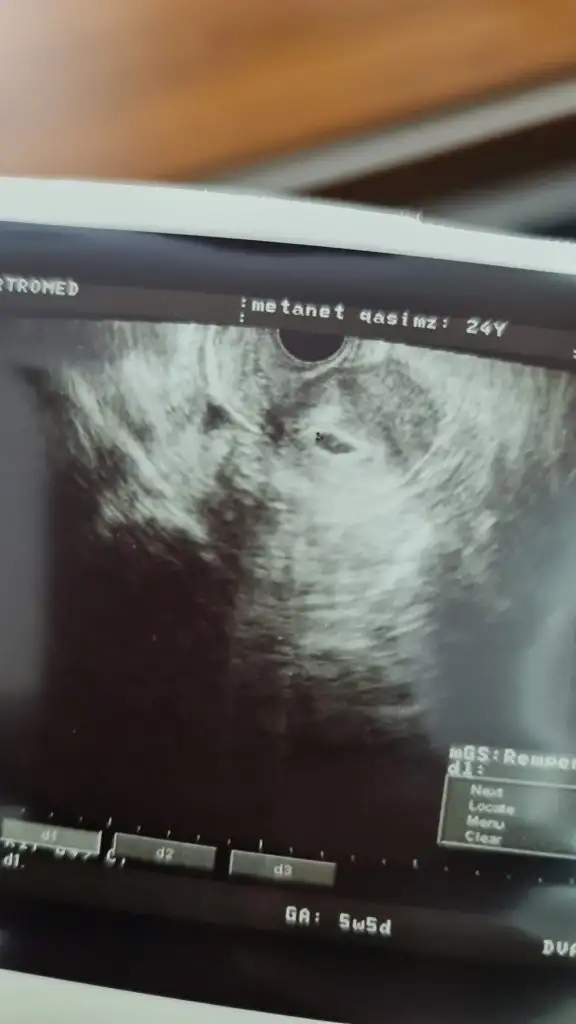

merhaba hanimlar. lutfen çok sikinti icindeyim. 5+5 hamileyim tüp bebek tedavisi. bu sabah kanamam başladı. doktora gitdim kese ve bebek göründü. ancak kanama durmuyor. lutfen yasamis olanlar cevaplarsa sevinirim.

M matanat ne yaptınız kanamanız kestimi bende aynı durumdayım şuan çok az leke geldi doktor gittim muaynede şakır şakır kanadı pıhtı düştü gitti dedim 2 saat yatırdılar sınra yine muayne etti 2 kese göründü ama hala kanamam devam ediyor ?